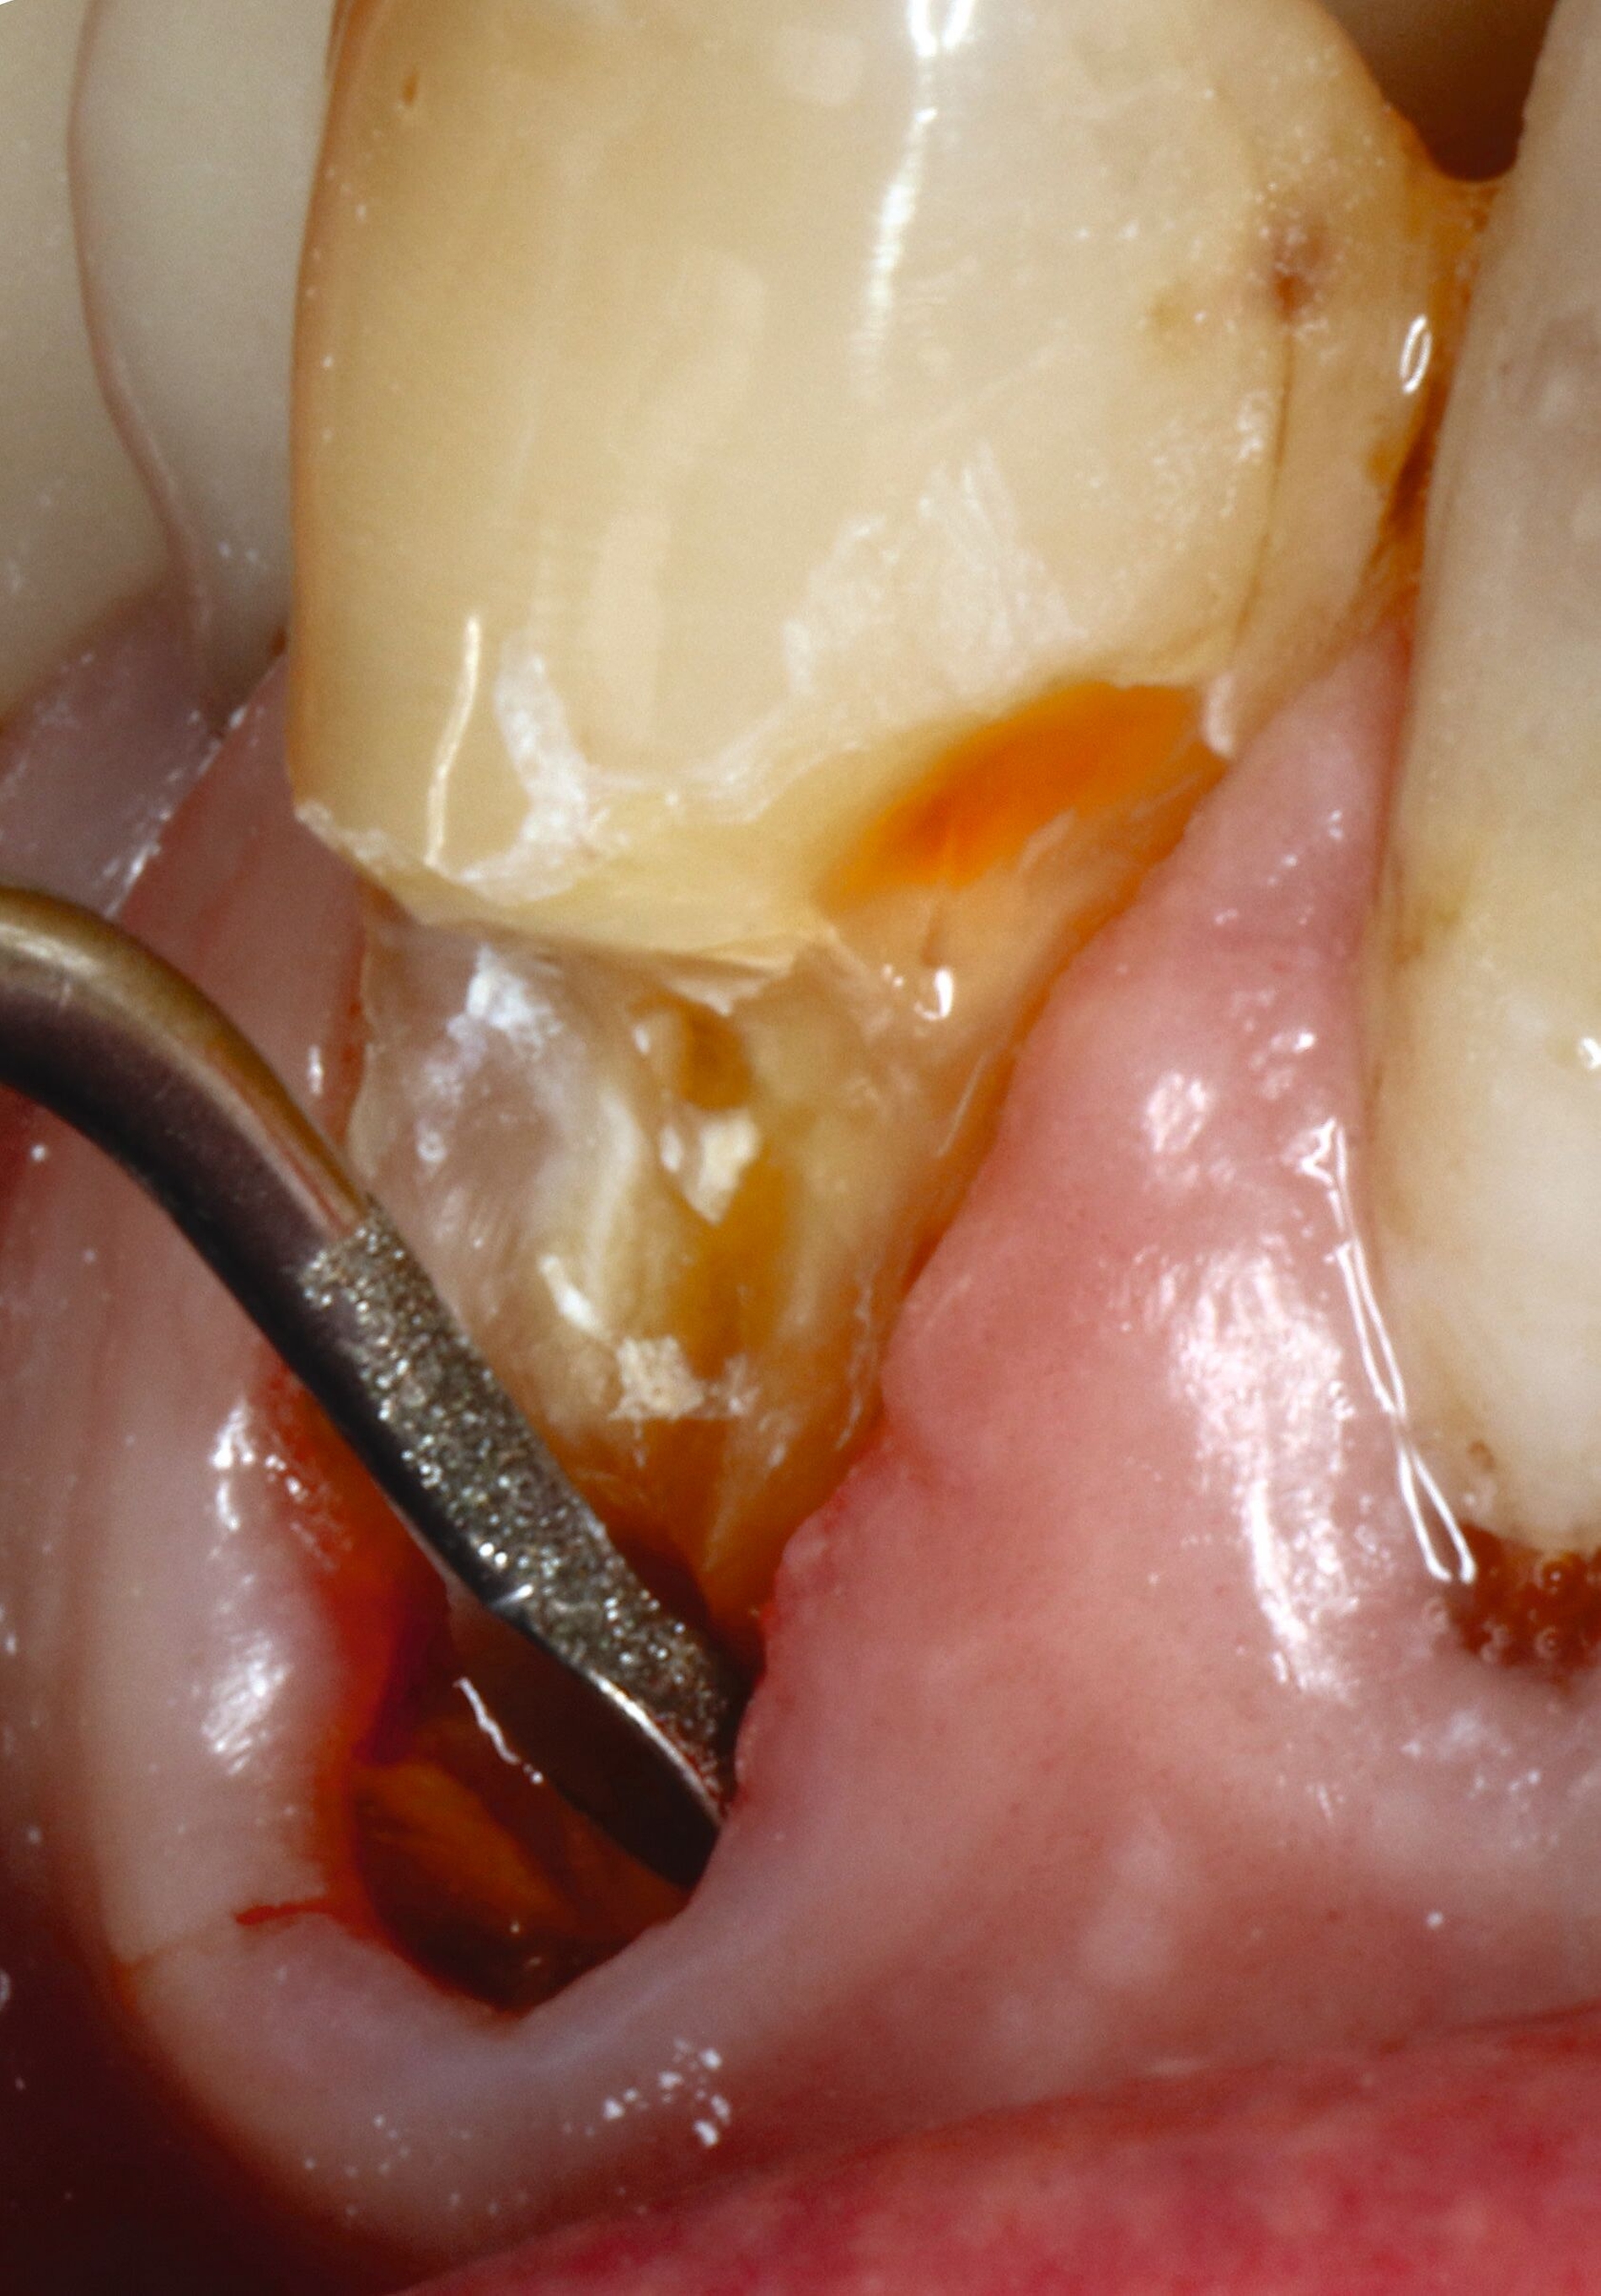

Abbildung 8 beschreibt einen Behandlungsablauf bei einer präexistenten Restauration an Zahn 23 mit deutlich sichtbarer Sekundärkaries zervikal und approximal (Abbildung 8a). Nach der Entfernung der alten Restauration (acht Jahre) zeigt sich das ganze schwer zu restaurierende Ausmaß des Defekts (Abbildung 8b).

Auf den ersten Blick ist klar, dass eine effektive Matrizentechnik hier schwierig wird, dass aber freies Schichten aufgrund der Nähe zur Gingiva ebenfalls keine gute Idee darstellt. Zur Kariesexkavation favorisieren wir schallschwingende, einseitig belegte Instrumente, die in der Regel keine Blutung provozieren, selbst wenn sie subgingival eingesetzt werden (Abbildungen 8c und 8d).

In solchen Fällen mit kaum zu kontrollierenden subgingivalen Rändern greifen wir vermehrt auf Stahlmatrizen zurück, die zervikal selbst bei extremen Fällen wie hier noch stabil nach subgingival geschoben werden können, die meist aber mit dem Finger fixiert werden müssen (Abbildung 8e). Bei dieser Technik ist es hilfreich, zunächst den subgingivalen Anteil mit einem gut fließenden Flowable zu füllen (Abbildung 8f), dann die Matrize abzunehmen, nachzufinieren, das Komposit sandzustrahlen und den breit angeschrägten Schmelz mit Phosphorsäure zu ätzen.